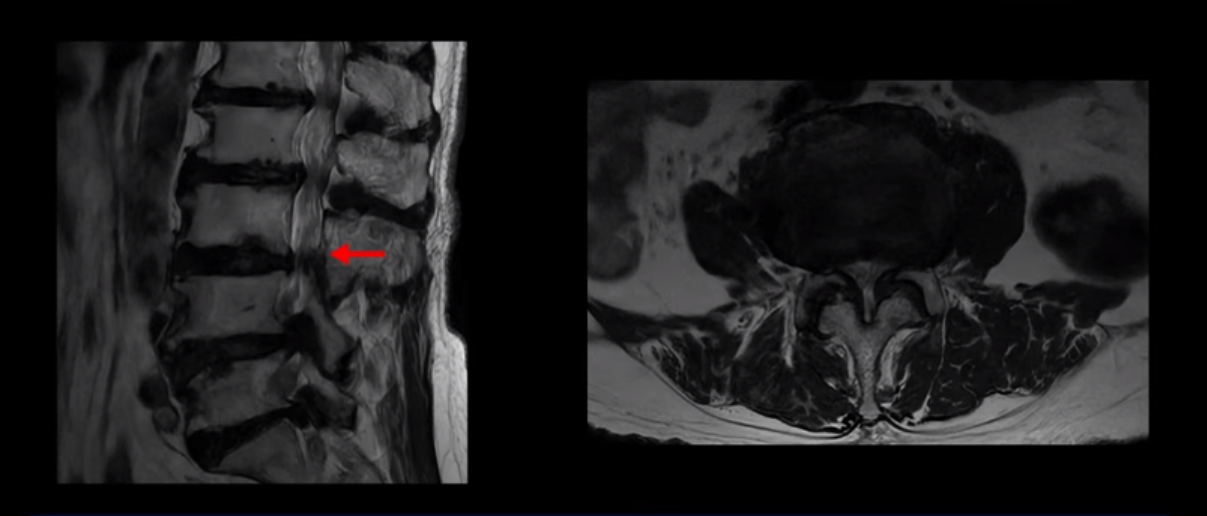

이 환자분은 MRI로 보면 허리 여러 마디가 신경이 매우 심하게 눌려 보이는 분입니다. 이분 MRI를 보면서 간단히 설명해 드린 후 어떻게 이렇게 신경이 심하게 눌린 환자분이 수술 없이 근육신경재활치료로 좋아질 수 있는지, 다리가 아파 걷지 못하는 환자가 어떻게 안 아프고 잘 걸을 수 있게 되는지, 10년 동안 괴로웠던 양 발의 시린 증상은 어떻게 사라질 수 있는지, 치료는 어떻게 하는지 자세히 설명 드리겠습니다.

MRI 보시면 (2-8) 허리의 5마디가 전부 다 심하게 퇴행되어 있습니다.

5마디 전부 다 심한 중심성 협착이 있습니다.

이렇게 모두 다 심하게 막히는 경우는 드문데요. 또한 오른쪽, 왼쪽 신경이 빠져나가는 추간공도 다 심하게 막혀있습니다.

오른쪽, 왼쪽 이렇게 신경 구멍들이 다 좁아지고 신경이 눌리니까 양쪽 다리가 발바닥까지 아파서 걷기 어렵고 양쪽 발이 10년 넘게 시린 겁니다. 당연히 수술해서 눌린 신경을 풀어줘야 한다고 들으셨는데요. 이런 환자분을 어떻게 수술 없이 치료할까요? 지금부터 설명해 드립니다.

실제로 수많은 논문에서 70세 이후 MRI로 협착이 보여도 아프지 않은 무증상 협착이 많다고 설명합니다. 협착이 있어도 안 아픈 사람들이 많다는데, 이게 왜 그럴까요? 근육 기능이 정상적이고 좋은 사람들은 근육이 허리를 잘 지지해 주니까 협착이 있어도 신경이 덜 눌리거나 안 눌리는 겁니다. 즉 근육이 좋으면 신경이 덜 눌리고 근육이 좋아지면 협착증이 좋아지는 겁니다. 그래서 저희가 근육 재활치료를 통해 근육의 기능을 회복시키면서 동시에 신경의 기능을 회복시키는 치료를 하는 겁니다. 이런 분들이 근육 재활치료를 통해서 협착증 증상이 좋아진다면 이런 분들의 협착증도 아프지 않은 무증상 협착으로 바뀌게 되는 겁니다.

이렇게 입원해서 치료하고 쉬고 운동하고, 치료하고 쉬고 운동하고를 매일매일 2주~4주 정도 계속 반복해서 근육 상태가 좋아지면, 허리를 더 잘 지탱해 주니까 신경이 덜 눌리게 되고 협착증 증상이 훨씬 더 좋아지게 됩니다. 이분은 3주 입원 치료를 받으셨습니다. 그럼, 이분의 3주 간의 근육신경재활치료 결과는 어떻게 됐을까요? 10년 동안 발이 시렸던 게 좋아졌을까요? 다리가 아파 걷지 못했는데 안 아프게 잘 걸을 수 있게 되었을까요?